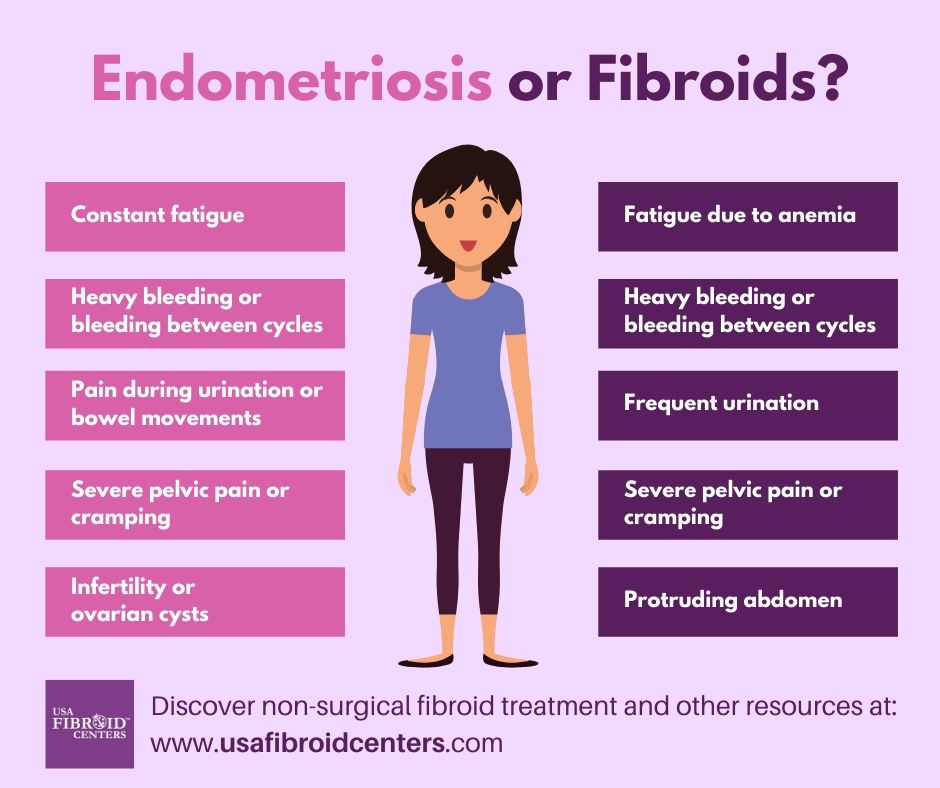

The Difference Between Fibroids and Endometriosis?